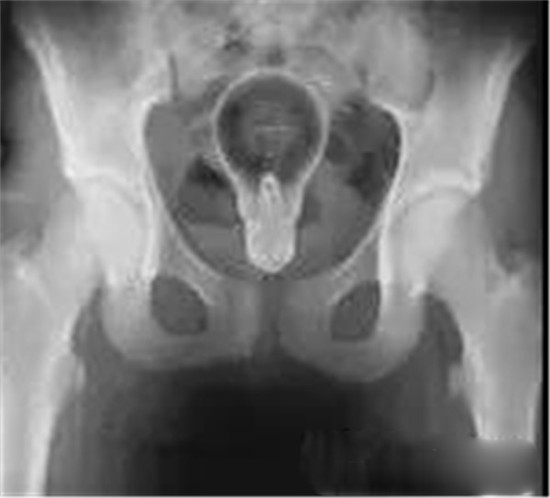

透视下从肛门里夹取直肠里的东西

医生给他检查的时候,发现已经有腹膜炎症状,怀疑肠梗阻,拍了个片子,就是上面那个片子:一条大黄鳝在肚子里。

考虑到他已经有腹膜炎的症状,说明肠子已经有个地方破了。只能动手术了。

把肚子打开后,发现大肠破了个洞,黄鳝的头,就在那个洞里。他肚子里都是大便。他的肠子水肿很厉害。黄鳝堵住了大肠,肠梗阻,导致大肠坏死穿孔了。

一般情况下,这些肛门异物的病人,来到医院后,医生都会给他上麻醉。把病人麻醉后,在透视下从肛门里夹取直肠里的东西。

一般情况下,用产钳可以取出大部分直肠异物。

如果从肛门里取不出,那就要开膛破肚了。